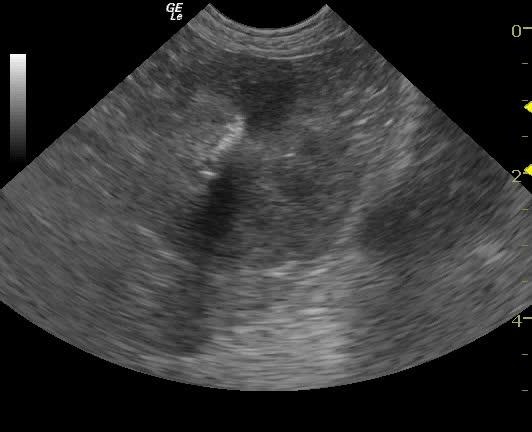

An 11-year-old SF Bichon dog was presented with a history of 3-4 days of lethargy, anorexia, and vomiting. Abnormalities on physical examination were tense abdomen, mild dehydration, and moderate dental tartar. Urinalysis (free-flow sample) showed inappropriate SG, (1.017), hematuria, and, pyuria. Abnormalities on CBC and serum biochemistry were leukocytosis, monocytosis, neutrophilia, azotemia, and hyponatremia.